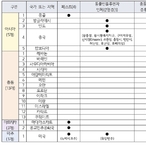

질병관리청, 2분기 중점검역관리지역 21개국 지정…4월 1일부터 시행

- 2026-03-24 08:54

- 노재영 기자